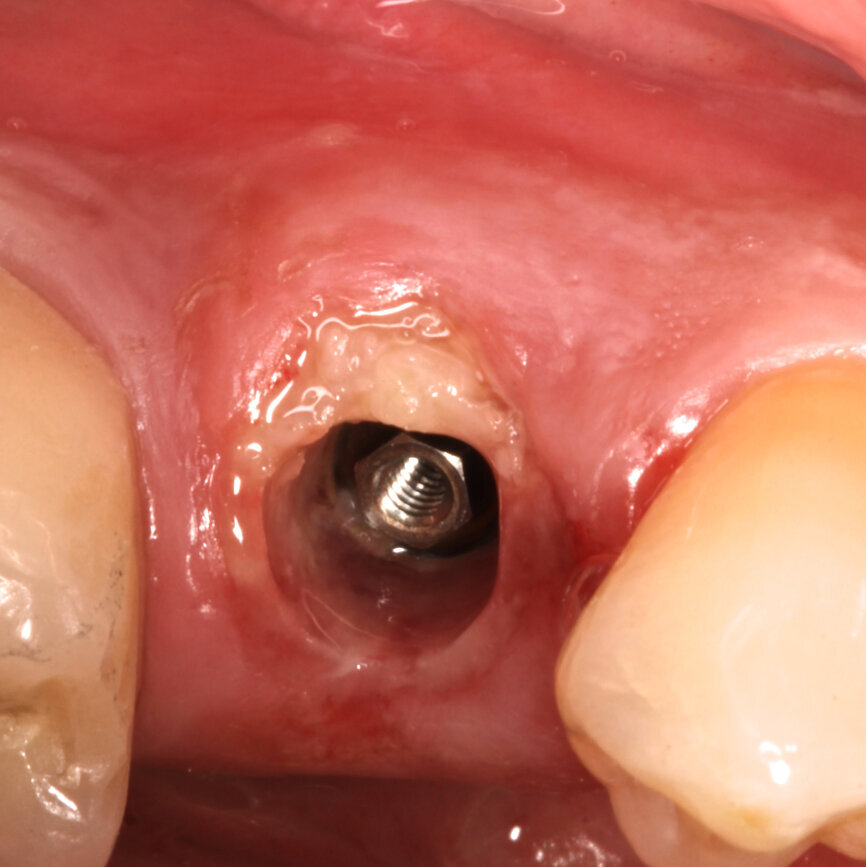

Fig. 3: Implant without intermediate abutment.

A 5 x 15 mm BTI interna plus implant (internal connection) was placed lingually to the SS, taking as reference for 3D positioning the adjacent tooth and implant crowns. The platform of the implant was placed 1 mm below the level of the buccal bone crest and the SS (Fig. 3). A BTI UNIT Transepithelial abutment was used to extend the implant’s platform 0.5 mm subgingivally (Fig. 4).